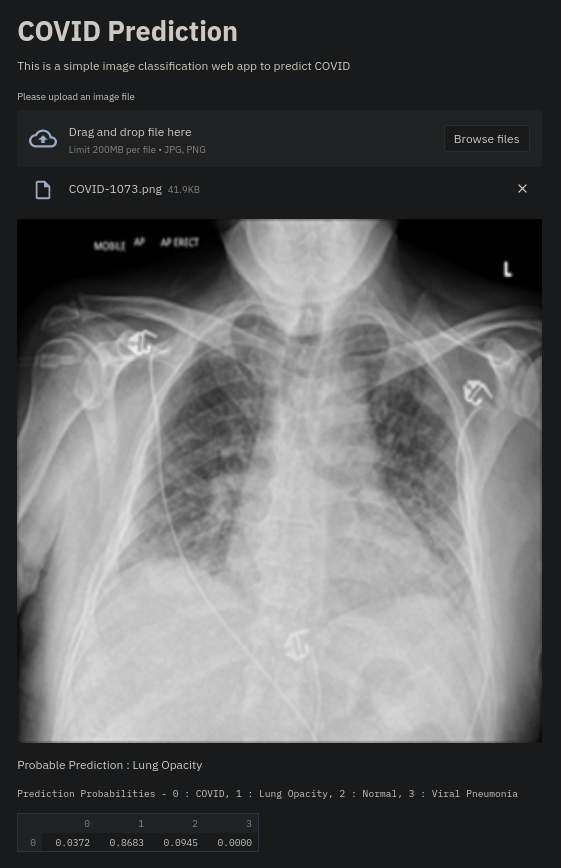

Currently, there is an urgent need for efficient tools to assess the diagnosis of COVID-19 patients. In this project, we propose a constructive solution for detecting and labeling infected tissues on CT lung images of such patients. To cut down false positives our model is trained on 4 types of lung CT images : COVID, Viral Pneumonia, Lung Opacity and normal images to get the best possible results with highest accuracy.

We built it using Tensorflow 2.x using Python. We have developed a Convolutional Neural Network model with an average accuracy of more than 85%.